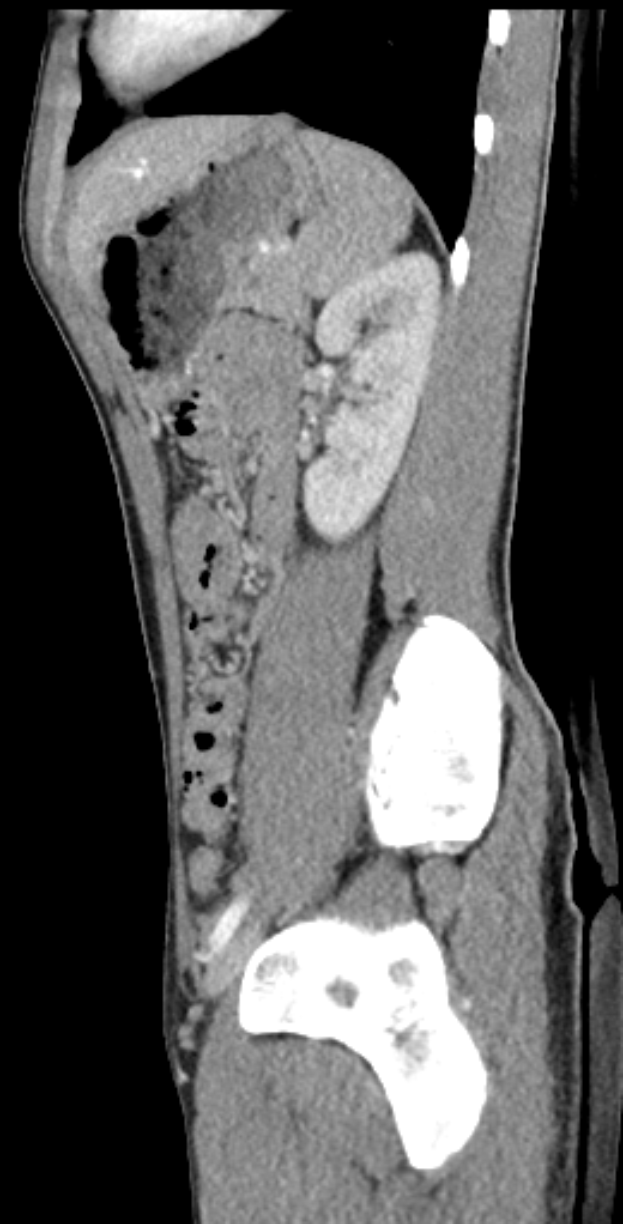

Eine MRT-Aufnahme eines Knies mit einem Bruch in der Mitte, umgeben von einem dunklen Hintergrund.Samira Striebitz